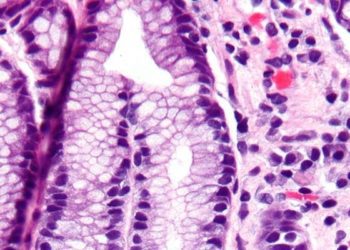

Image: PD 1. Histamine-2 receptor antagonists (H2RAs) were associated with lower risk of developing a secondary gastrointestinal (GI) hemorrhage, pneumonia, ...